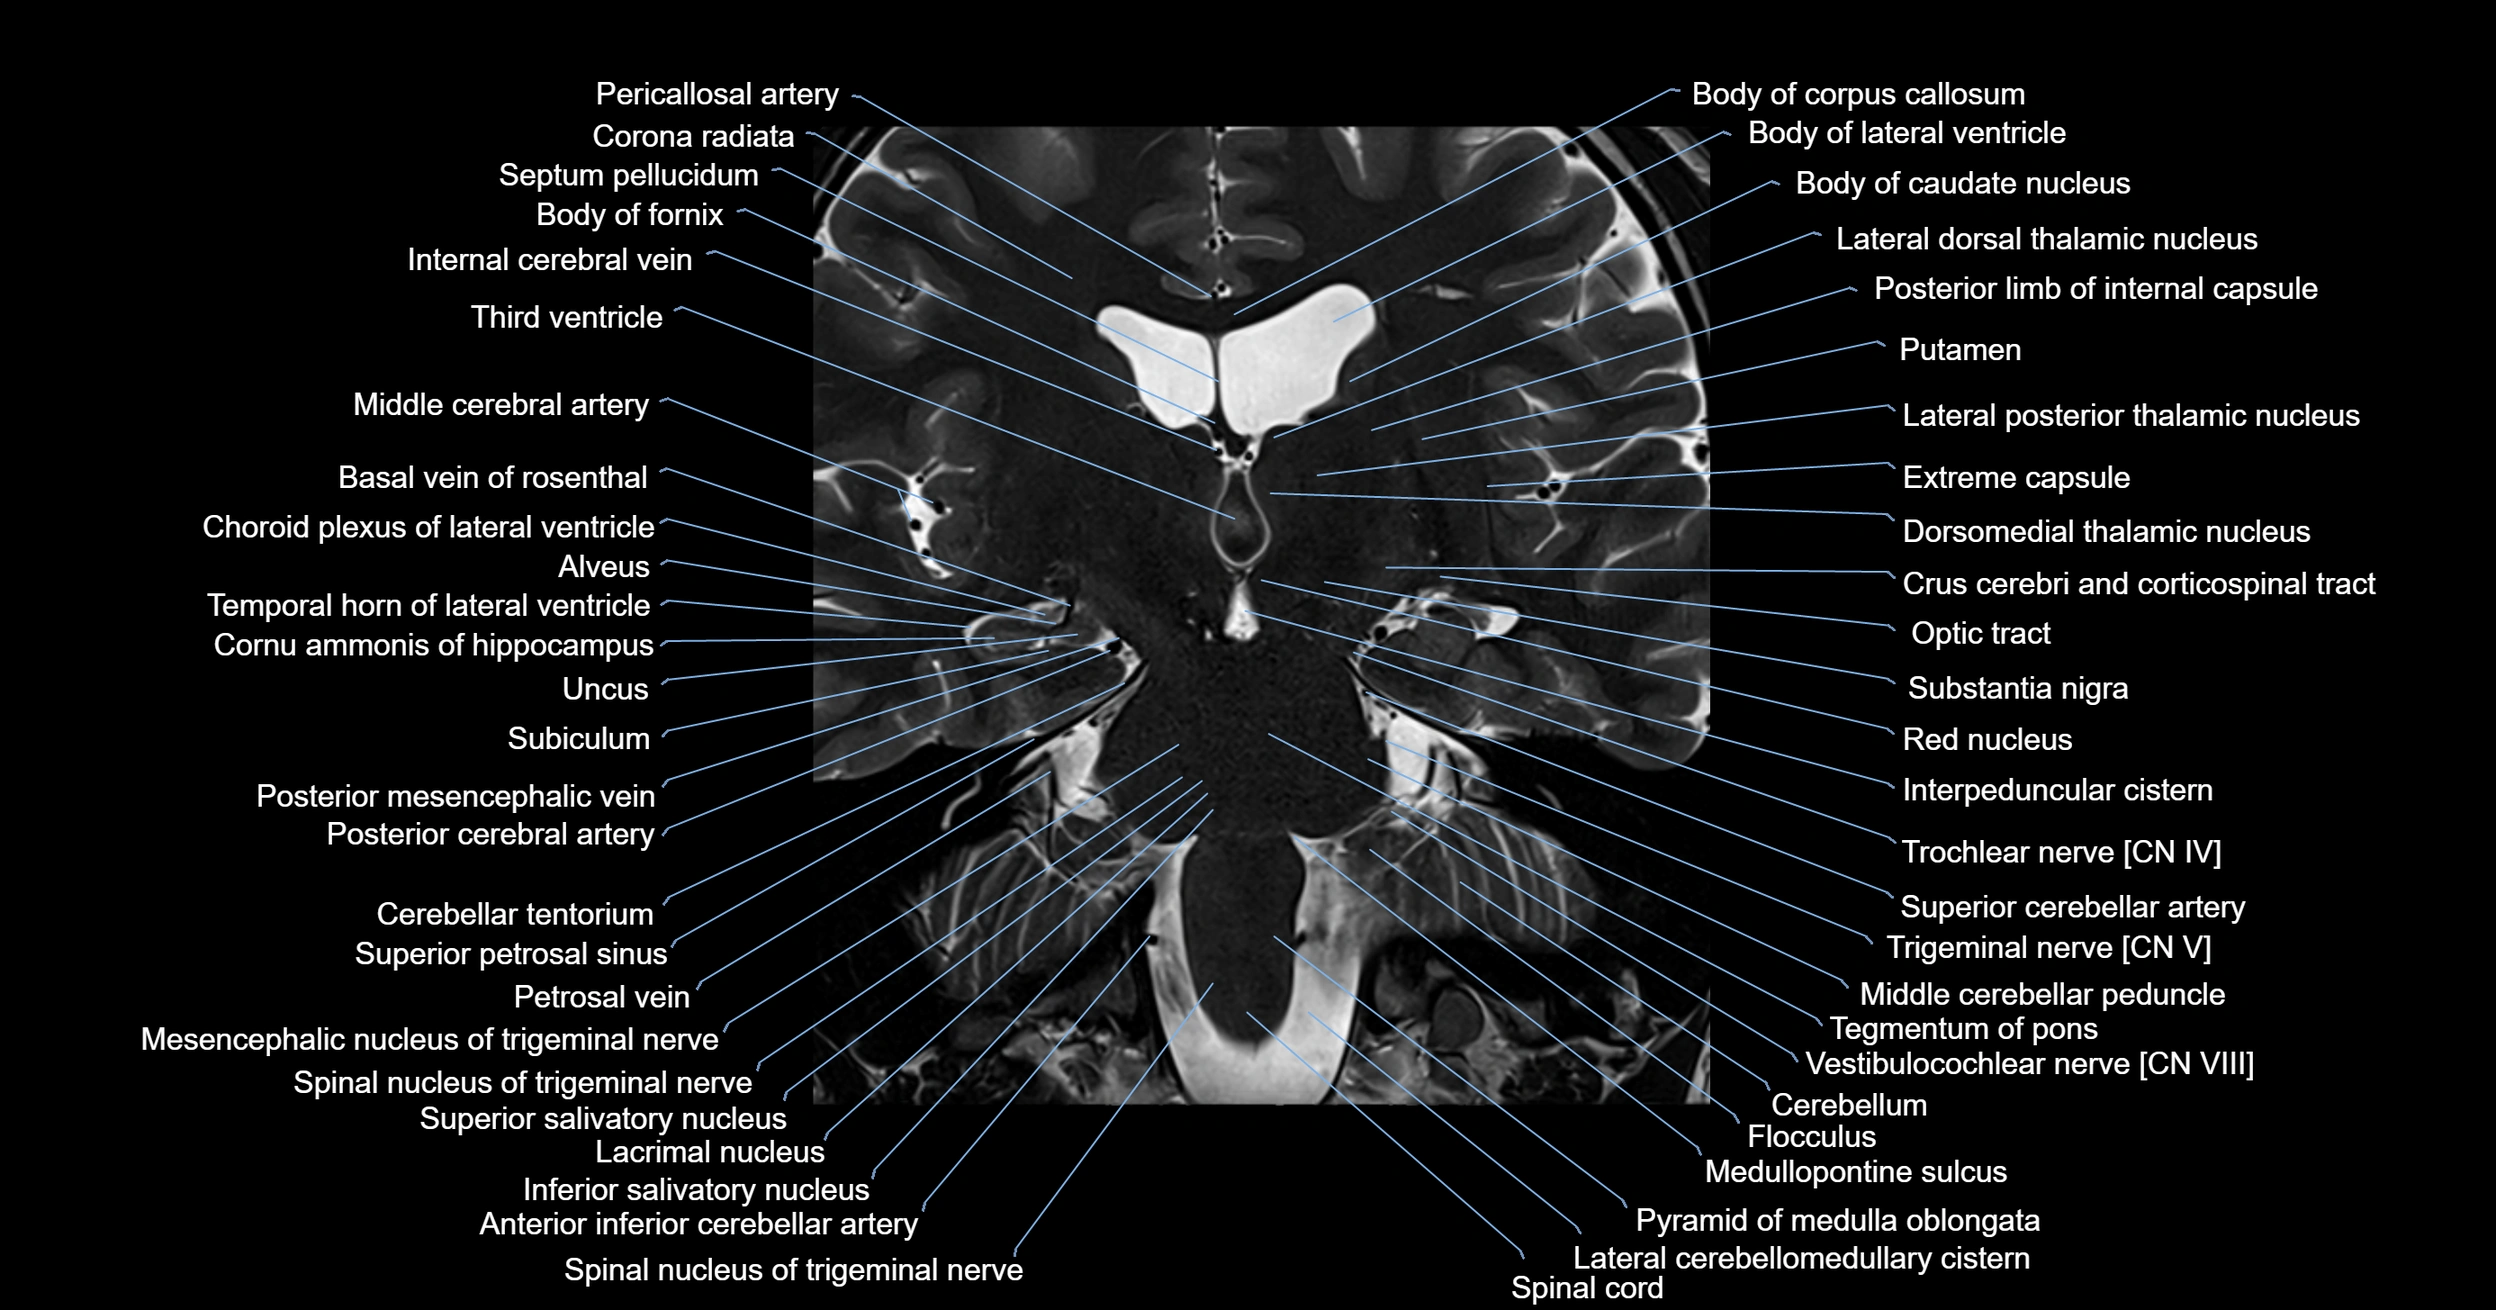

MRI images